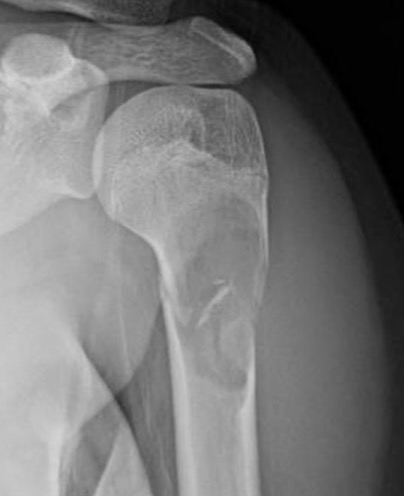

X-ray

Well-defined lucency

- thin sclerotic rim

- usually central

- thinned cortex with slight expansion

- thin internal septa

- can be multi-loculated

Fallen-Leaf (AKA fallen-fragment)

- with pathological fracture

- indicates that the lesion has no matrix and is fluid filled